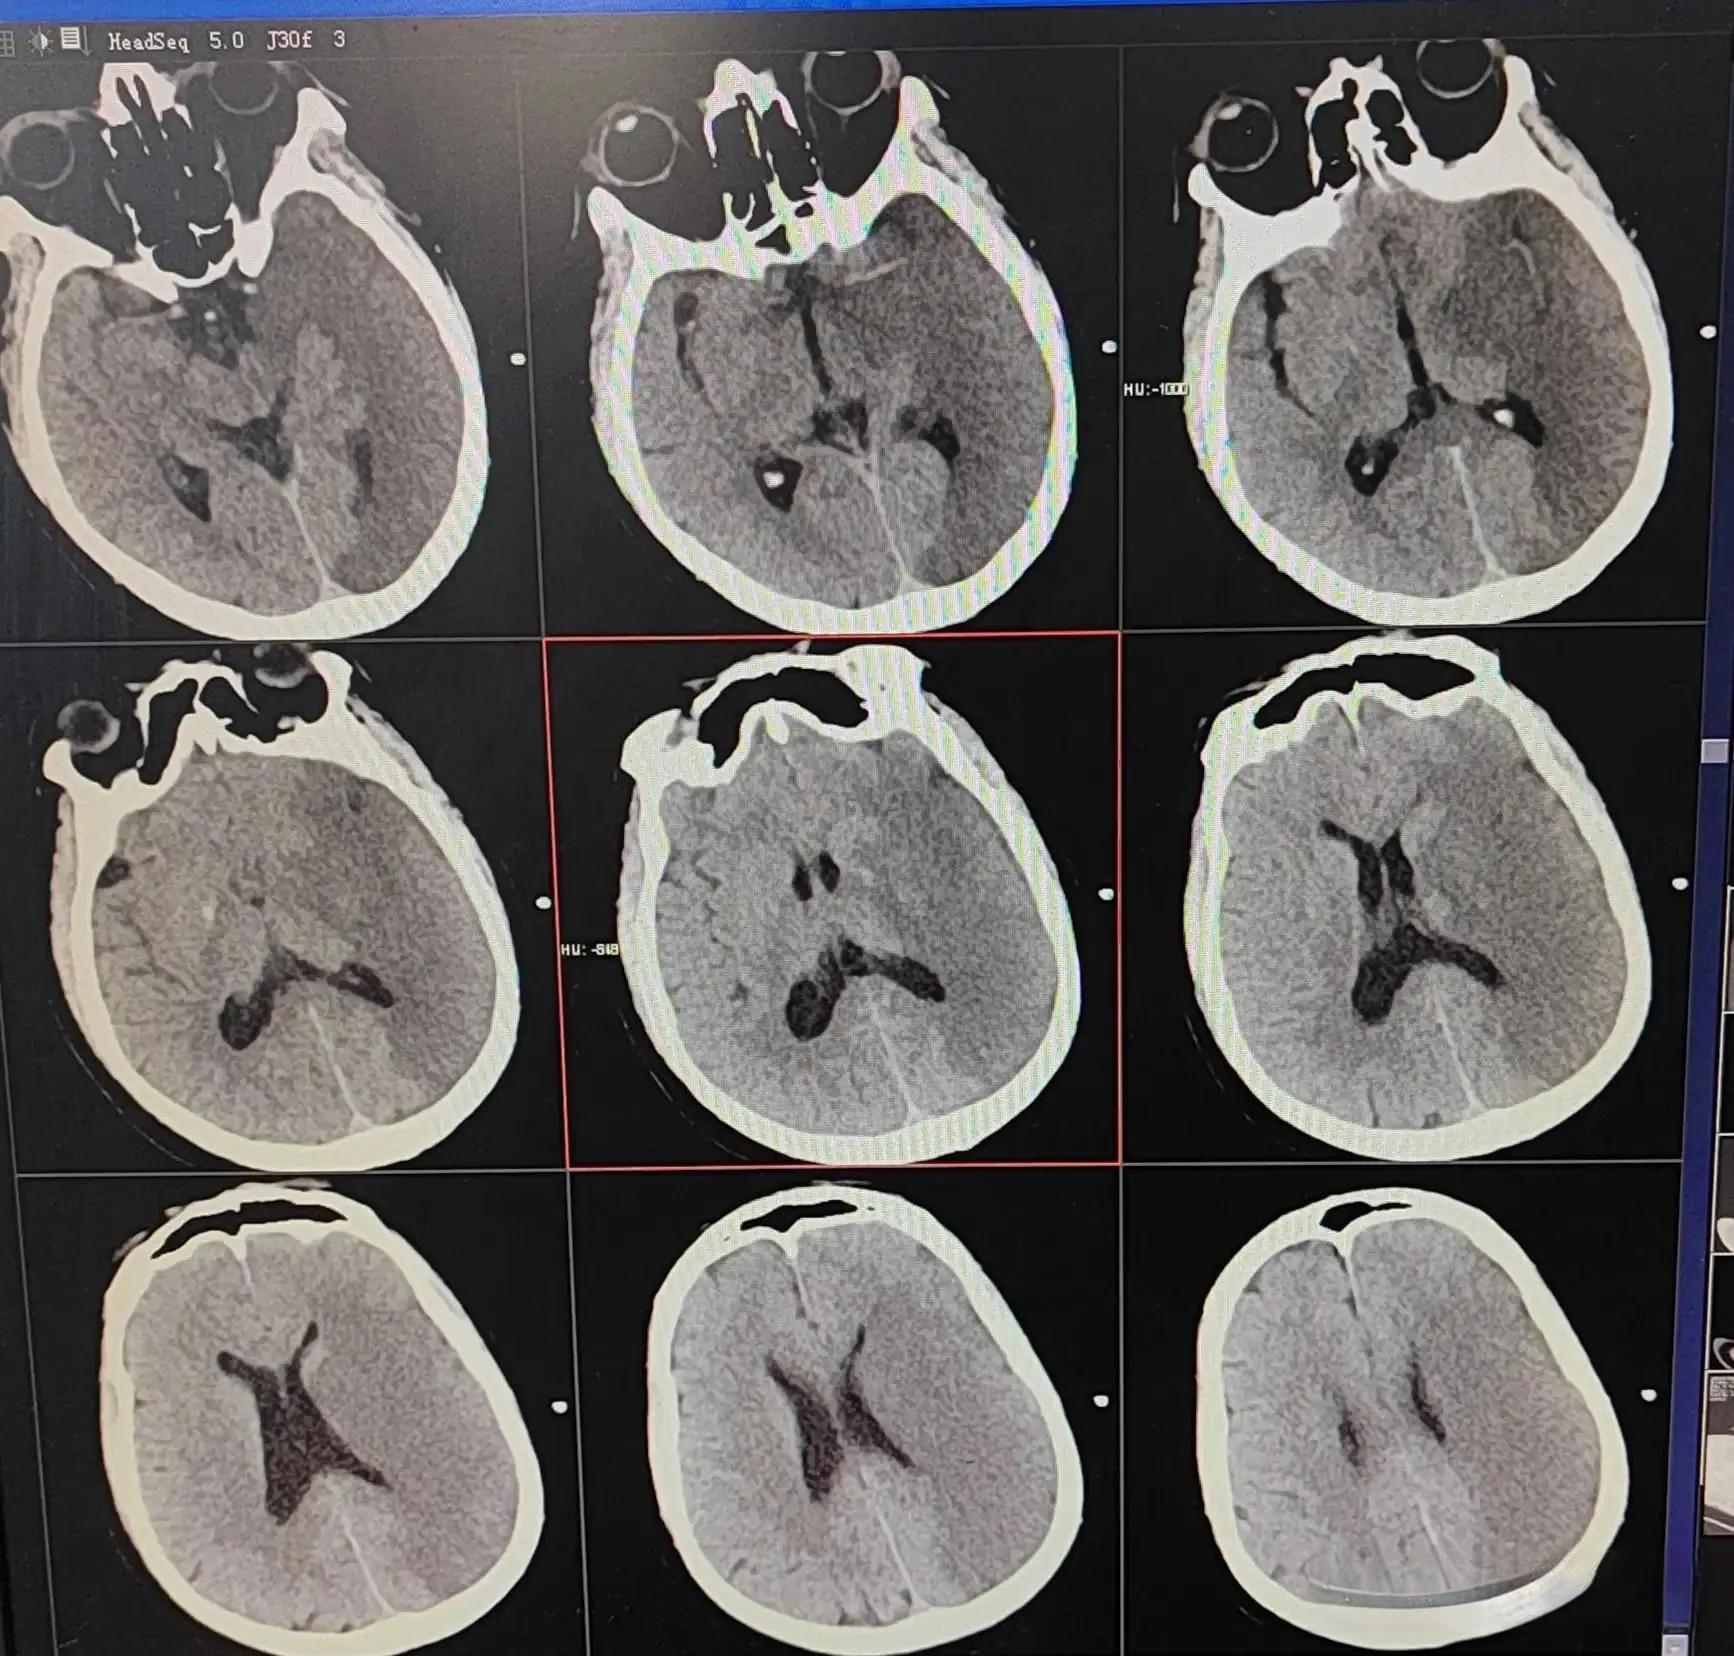

大面积脑梗是一种极其凶险的疾病,约占所有脑梗死的2% 8%,病死率高达60% 80%。面对这种危急情况,医生们常常需要“见招拆招”,灵活运用各种治疗方法,与时间赛跑,与死神抗争。